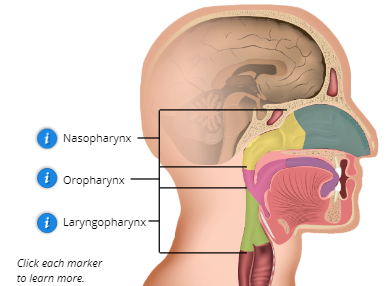

Pharynx

located behind the nasal cavity and mouth; connects nose, mouth, and larynx; functions as a passageway for air moving from the nasal cavity to the larynx and food moving from the mouth to the esophagus

Name the 3 Parts of the Pharynx

Nasopharynx, Oropharynx, and Laryngopharynx